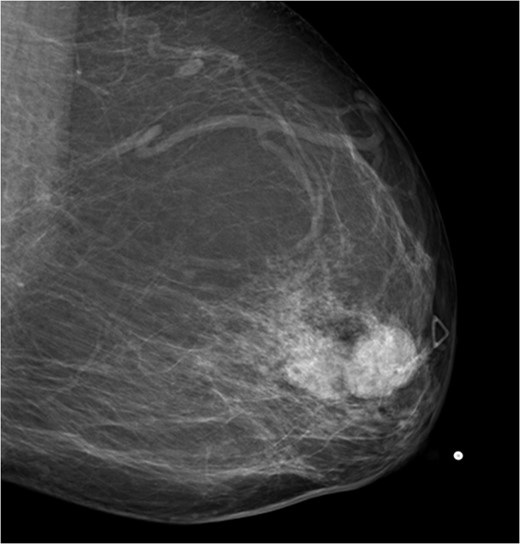

The patient was then sent for MRI of the breast to detail the extent of the remaining mass. This revealed an ill-defined mixed linear and fine nodular enhancing tumor 6.5 × 4.6 × 4.8 cm in size with BI-RADS 5 (Figs 4–7).